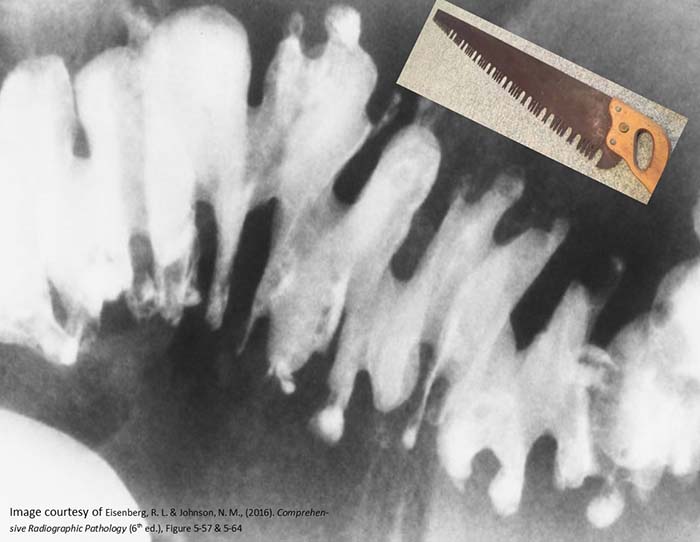

What are diverticula?

Outpouchings (herniations) of the mucosal layer through a weakened muscular layer of the bowel wall.

Herniation of the mucosal layer through weak areas in the muscular wall of the colon.

Where do diverticula usually form along the bowel wall?

At sites where mesenteric vessels penetrate the bowel wall, near the tenia coli.